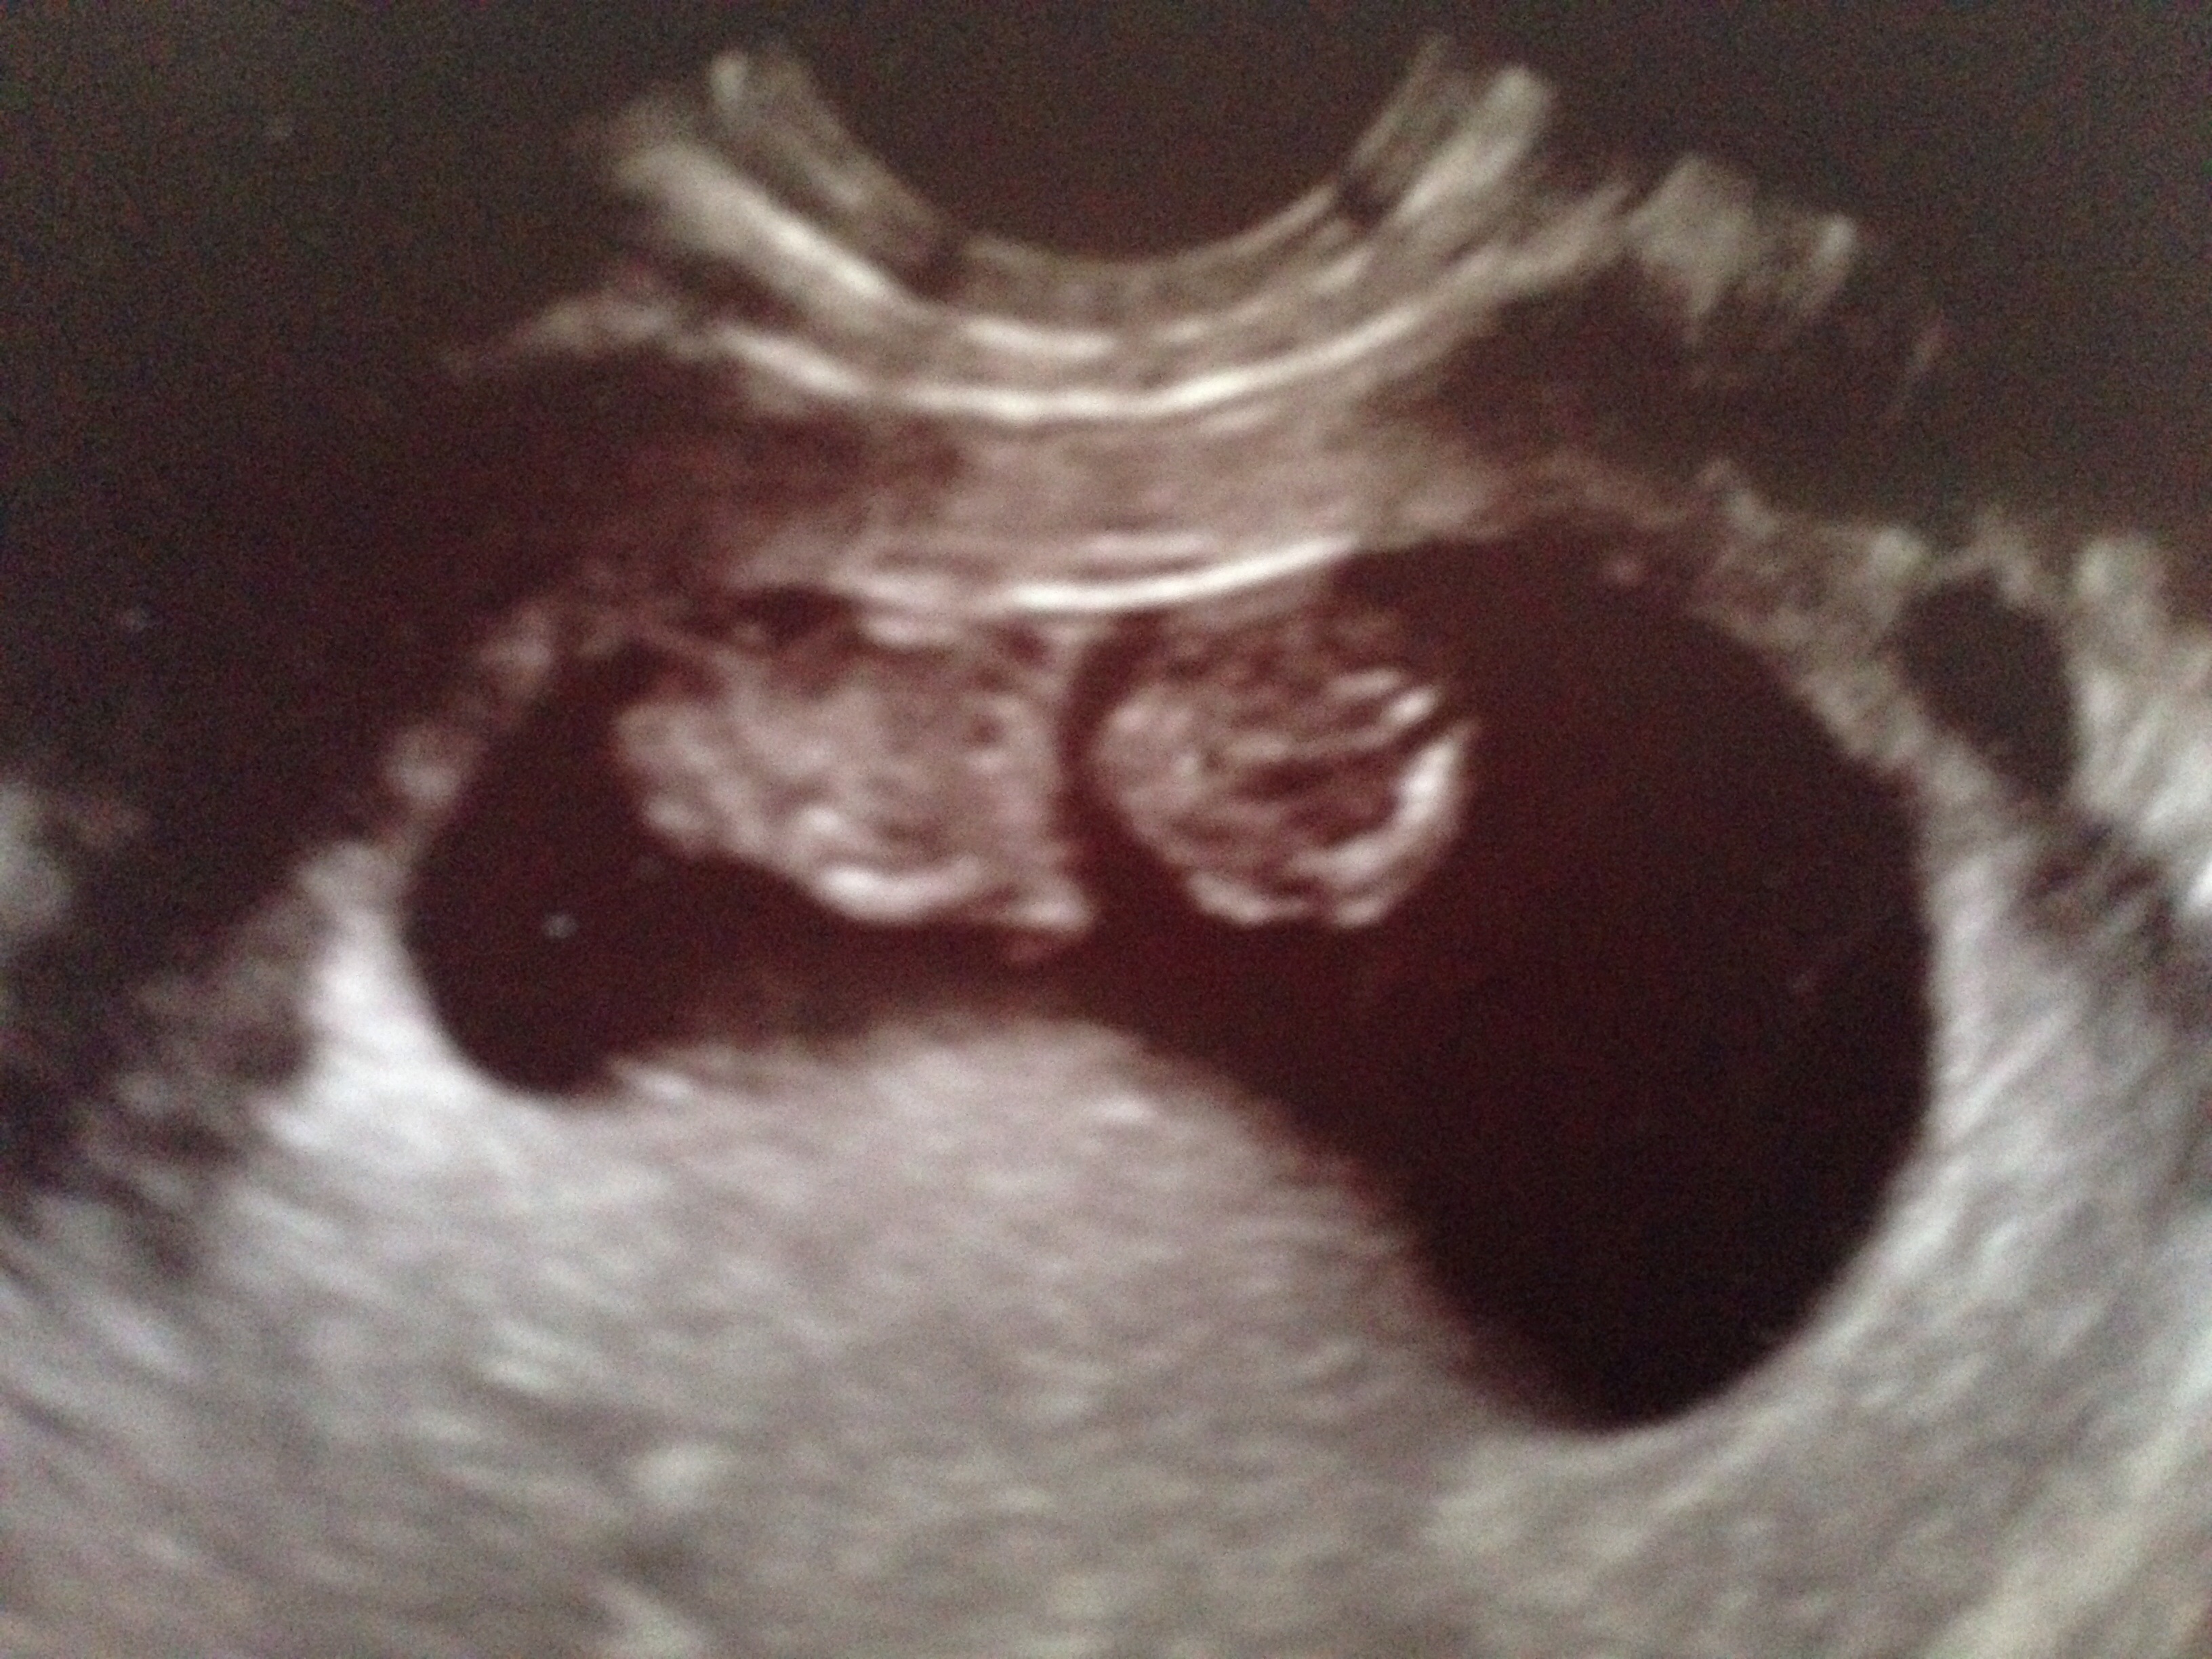

TTC 31\2 years 20 medicated cycles of some kind, 8 failed IUIs (every med combo possible) 5/14/14 IVF # 1, 6dp5dt BFP, Betas 8dp5dt- 67, 14dp -670, 17dp -1761, 20dp-4858, 27dp-28,800 6/11/14 6w3d Twins!!! - EDD Feb 1st

20 medicated cycles of some kind, 8 failed IUIs (every med combo possible)

5/14/14 IVF # 1, 6dp5dt BFP,

Betas 8dp5dt- 67, 14dp -670, 17dp -1761, 20dp-4858, 27dp-28,800

6/11/14 6w3d Twins!!! - EDD Feb 1st